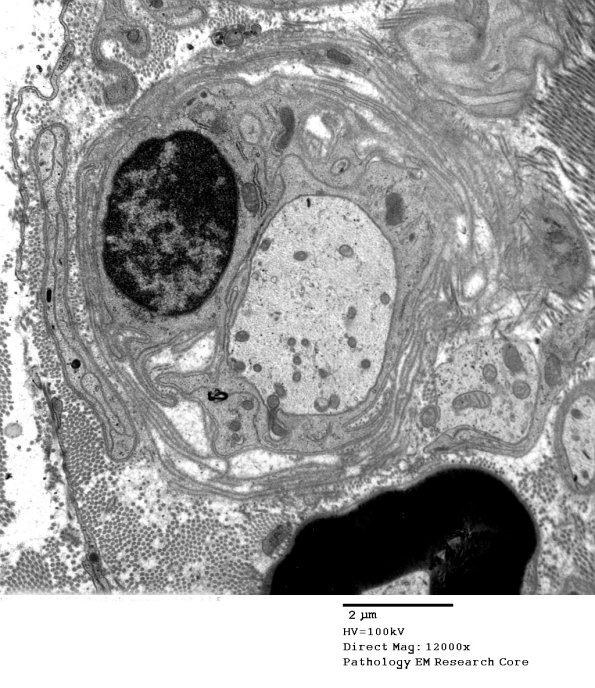

Multiple examples of demyelinated large axons, many surrounded by numerous delicate macrophage processes. (electron micrographs)